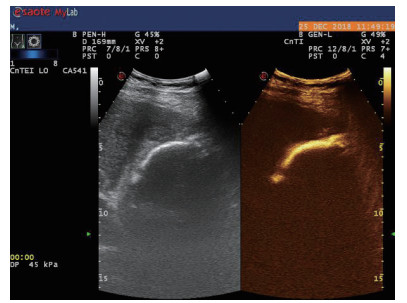

图 2 穿刺后经引流管超声造影,显示置管路径(箭头处)

术后再次经肘静脉超声造影同时经引流管超声造影:PTGBD后,再次经肘静脉快速团注SonoVuel 2 mL,在造影成像模式下进行观察肝脏被膜、胆囊床穿刺路径有无造影剂外渗,腹腔内有无外渗凝聚的造影剂,判断有无活动性出血及出血程度,如判断出血速度快、出血量较大,考虑动脉性出血,及时改为开腹或腔镜手术止血。PTGBD术后经引流管超声造影,置管成功后快速抽出胆囊内残留胆汁,减轻胆囊压力后,在超声造影模式下直接经引流管注入配制待用的稀释声诺维造影剂20 mL,实时动态的观察造影剂在胆囊腔内的充盈范围(图 23),评估引流管的通畅程度及引流范围、观察其在胆囊腔内的位置走形及卷曲情况、观察胆囊周边及腹腔内有无造影剂外渗。如患者腹痛症状加剧,结合经引流管超声造影判断有胆汁漏出表现,应持续监测观察患者生命体征及保守治疗效果,必要时及时改行开腹或腔镜手术治疗。